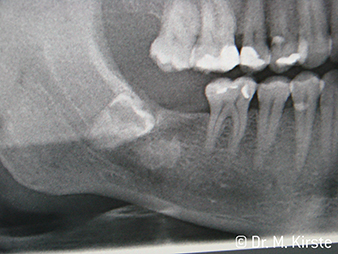

Por primera vez, los instrumentos de transmisión WS-91 y WS-91 L G combinan las ventajas de las piezas de mano y los contra-ángulos quirúrgicos (Figura 1). Al haber ampliado el ángulo hacia el panel frontal entre la zona del mango y el eje de la fresa, se permite un buen acceso a la dentadura tanto bucal como oclusal (Figura 4). Los dientes desplazados pueden extraerse fácilmente (Figuras 6 y 7). Además, el doctor percibe mucho mejor el campo de operación que con los instrumentos disponibles anteriormente. A este respecto, el Dr. Mario Kirste de Fráncfort del Óder (Alemania) comenta: «Cuando giro ligeramente el cabezal del contra-ángulo, puedo trabajar de forma rápida y segura en la zona retromolar. El instrumento tiene el potencial de agrupar las diferentes posiciones necesarias tanto para los usuario de contra-ángulos como los de piezas de mano». (Figuras 2-5).

Una de las aplicaciones de los contra-ángulos WS-91 / WS-91 L G es la apicectomía. Su sofisticada ergonomía garantiza una buena visibilidad también en los casos de los molares superiores y en bocas pequeñas. Con el WS-91 L G se incorpora un mini LED+ que ilumina el campo de operación con toda claridad. El Dr. Kirste comenta: «Los nuevos contra-ángulos son realmente una buena solución. Esta maravilla técnica de W&H mejora el ángulo de visión y las posibilidades en la cirugía diaria.»